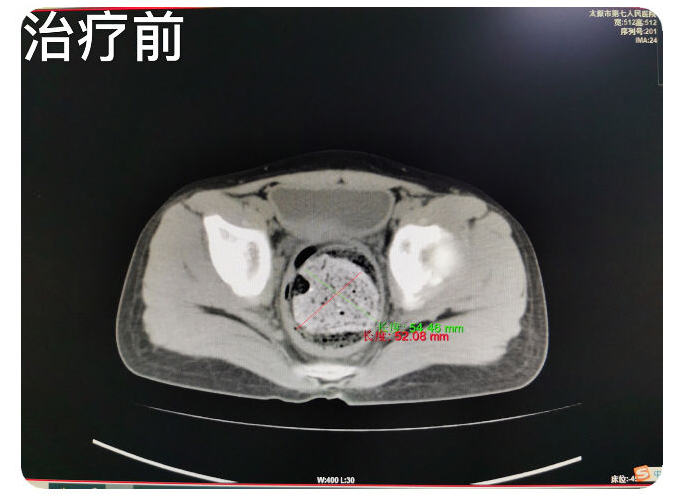

患儿九岁,主因排便控制不佳两月余,辗转就诊于省内多家二人麻将 ,未明确诊断,治疗效果欠佳,肛门失禁症状逐渐加重,患儿及家属均承受了极大的心理及经济负担,后来患儿家属慕名就诊于二人麻将指南网 翟春宝主任医师门诊。翟主任通过仔细询问病史,细致查体后,考虑为粪性嵌塞引起的肛门失禁。入院检查CT,确认患儿直肠、乙状结肠高度扩张,内有高密度巨大粪块经过讨论为患儿制定了个体化的综合治疗方案。并就患儿的病情与家属充分沟通,缓解了患儿及家属的焦虑情绪,增强了患儿家属对治愈疾病的信心。经过10余天的规范化综合治疗,患者粪性嵌塞较前明显好转,仍有部分肠管扩张,肛门失禁症状得到治愈,无不适主诉,达到出院标准。